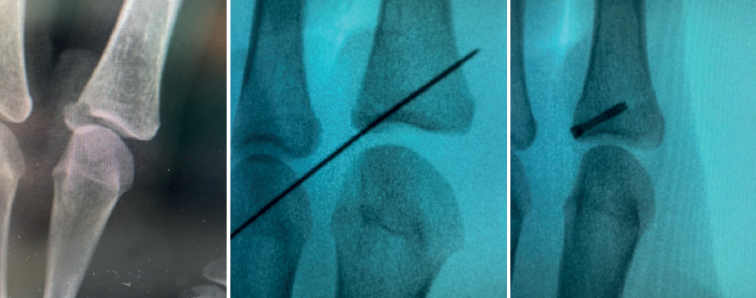

- Fractures with avulsion of the insertion of the collateral ligament (Figures 2 and 3).

In terms of treatment, different authors advocate debridement of the insertional area of the ligament, reduction and correct positioning of the bone fragment, and its percutaneous fixation with Kirschner wires(1). Other authors advocate arthroscopy to locate and prepare the ligament and, by means of a minimal incision, re-anchor it(9).

Arthroscopically assisted reduction and percutaneous fixation of the avulsed fragment has several advantages over the open technique(5), including minimal aggression to the joint capsule, which usually serves to shorten the rehabilitation period. Furthermore, although not the subject of our study, the aesthetic result is more pleasing.

Once the fragments have been reduced, 0.8 or 1.0 Kirschner wires are used to maintain reduction (Figure 7). Sometimes we can only maintain reduction by applying a stop, to prevent the osteochondral fragment from collapsing. Depending on the fracture pattern and the surgeon's preference, we can use conventional screws, cannulated screws, etc. (Figures 8 and 9).